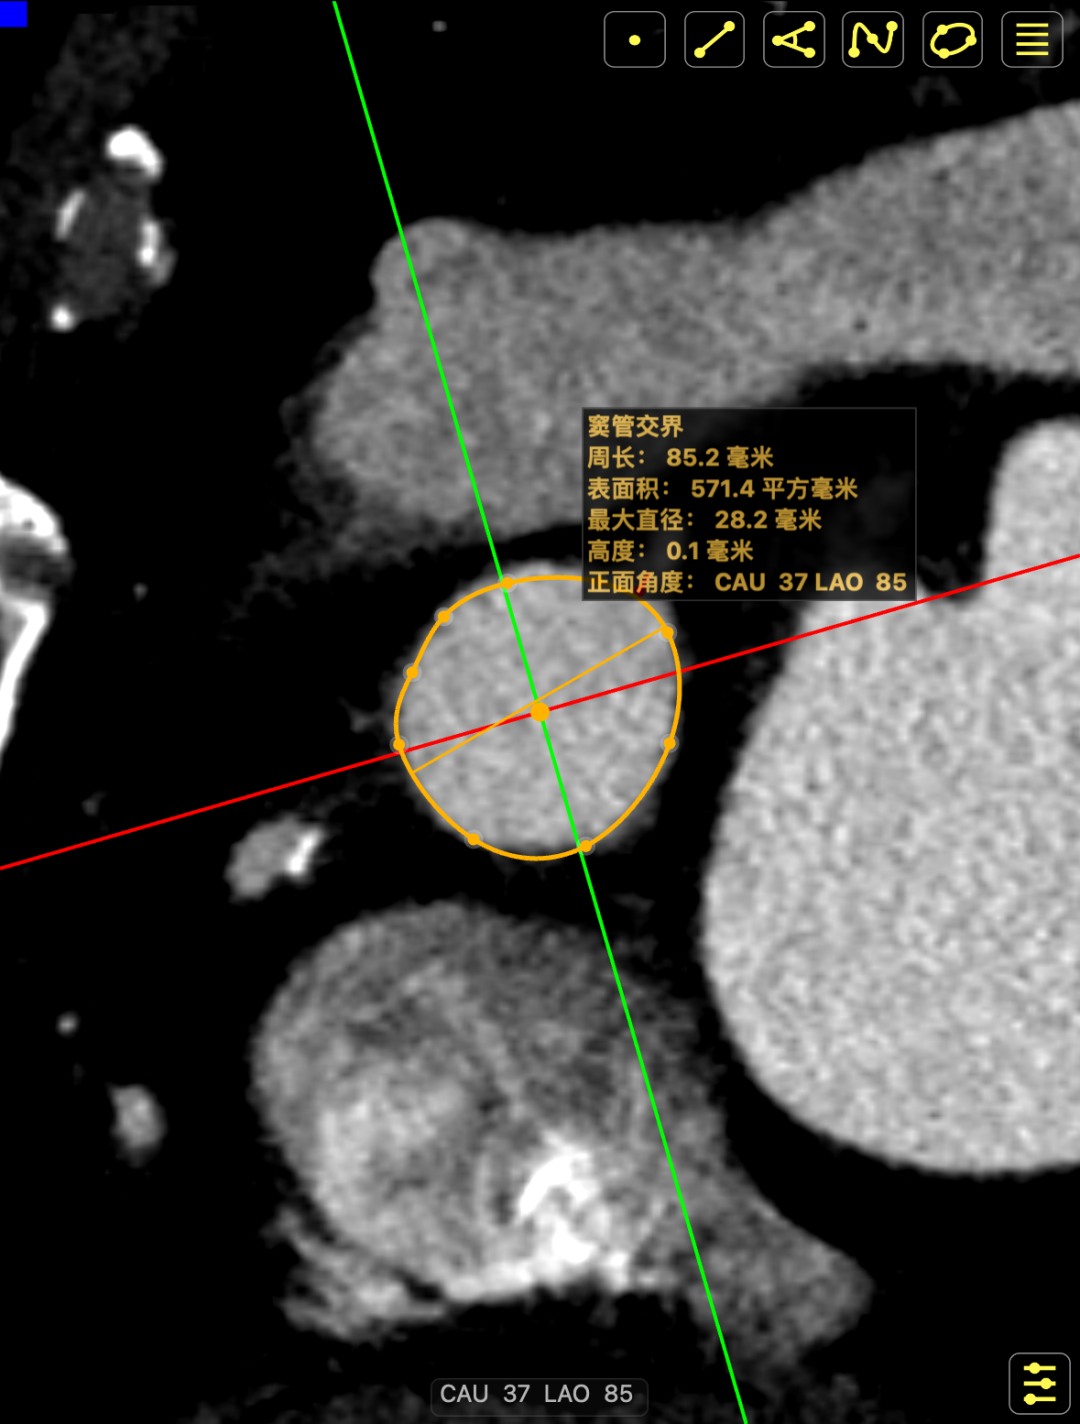

CT影像

CT影像